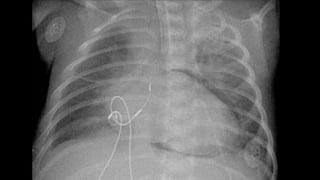

SINAL DO SULCO PROFUNDO

PNEUMOTÓRAX + PACIENTE SUPINO → SULCO PROFUNDO